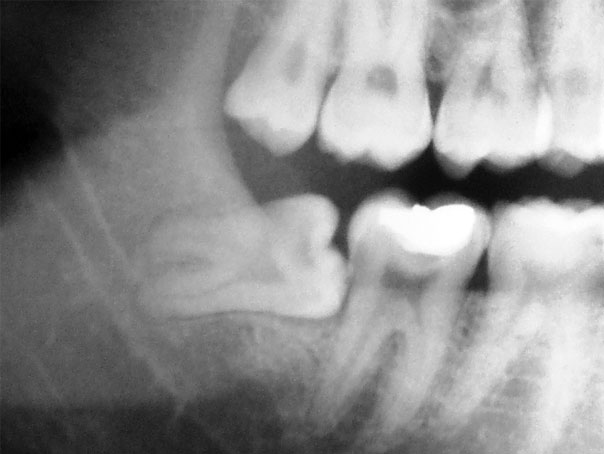

Los terceros molares retenidos (o muelas de juicio) son las últimas muelas en erupcionar en la boca. La dieta moderna y la popularidad de la ortodoncia producen un arco que comunmente no deja espacio para que los terceros molares erupcionen. Un diente se retiene o impacta cuando hay falta de espacio en el arco dental y su crecimiento y erupción son impedidas por la mucosa subyacente, el hueso u otro diente. Estos pueden ser dolorosos u ocasionar infecciones dañando elementos dentarios próximos, como también otros problemas más serios pueden ocurrir si el saco que los rodea se llena de fluidos formando un quiste, o raramente un tumor en sus paredes.

Para realizarse la cirugía no es recomendado esperar a que empiecen a molestar. Una temprana remoción puede resultar en una cicatrización menos complicada, recomendando que la cirugía se realice cuando el paciente es joven adulto para prevenir futuras complicaciones.